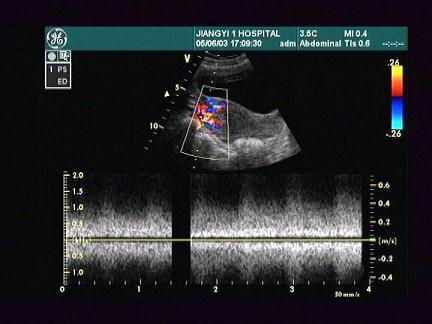

女,24岁,人流术1个月后阴道不规则出血。根据超声所示,应考虑为?(?)A.宫内残留B.葡萄胎C.绒癌D.早孕E.子宫肌瘤

问题 女,24岁,人流术1个月后阴道不规则出血。根据超声所示,应考虑为?(?)

选项 A.宫内残留 B.葡萄胎 C.绒癌 D.早孕 E.子宫肌瘤

答案 A